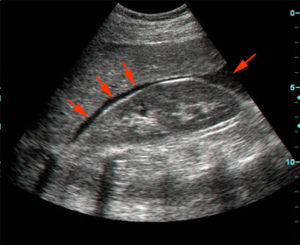

Focused abdominal sonography in trauma (FAST) should be used in any hemodynamically unstable trauma patient to document fluid in the pericardial sac, hepato-renal fossa, spleno-renal fossa, and pelvis. FAST is a rapid-non-invasive technique that can be performed at the bed side and can be repeated whenever requested.

FAST is helpful in the evaluation of patients who are hypotensive post-trauma and can generally classify patients into those requiring urgent laparotomy from those who do not depending on the presence of fluid in any of the previously mentioned four compartments examined in FAST.